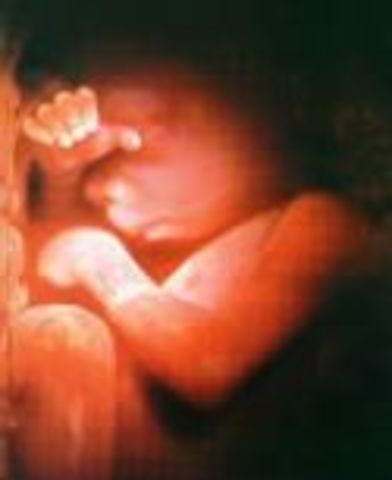

The baby fuzz, lanugo, is disappearing. Your baby drinks about a pint of amniotic fluid a day. You may gain a pound a week (500g) for the rest of your pregnancy. Half of your weight gain will go directly to your baby.

Your child has now an excellent chance of survival outside the womb. Fat accumulations plumps up the arms and legs this week.

The body of your baby is growing round due to developing fat layers. Your baby's reflexes are coordinated. Lungs are almost fully developed. About 90% of babies born this week survive.